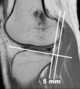

Anterior tibial compartment syndrome

A compartment syndrome is an increased pressure within a muscular compartment that compromises the circulation to the muscles. Symptoms and signs Diffuse tightness and tenderness over the entire belly of the tibialis anterior muscle that does not respond to elevation or pain medication can be early warning signs and suggestive of Anterior Compartment Syndrome. [Source: Wikipedia ]